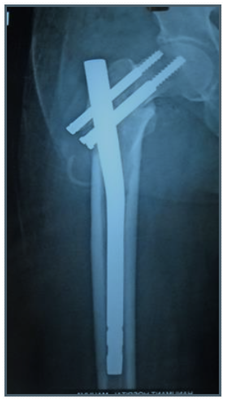

Indications (Figure 1)

1. Unstable IT fractures

1. Comminuted

2. Reverse oblique

3. Subtrochanteric extension

2. Associated shaft fracture

Figure 1 PFN in IT fractures.